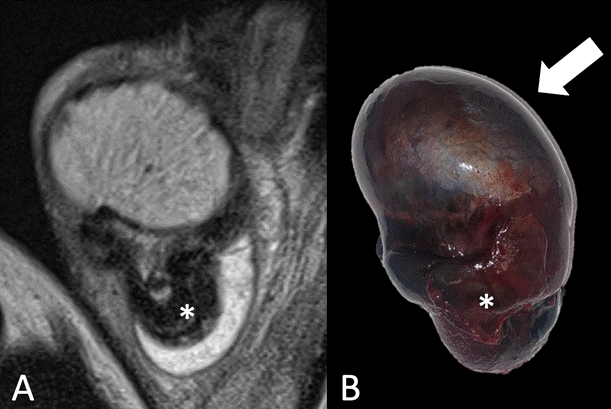

A) Imagen coronal secuencia T2 que muestra la torsión a nivel del cordón espermático (*). B) Pieza quirúrgica con vista frontal. Se observa el TD aumentado de tamaño con focos de necrosis a expensas del edema periférico (Flecha). Origen: Servicio de Diagnóstico por Imágenes. Hospital Italiano de Buenos Aires. Buenos Aires, Argentina. 2021.

Figura 3b Comparación RM-anatomía patológica